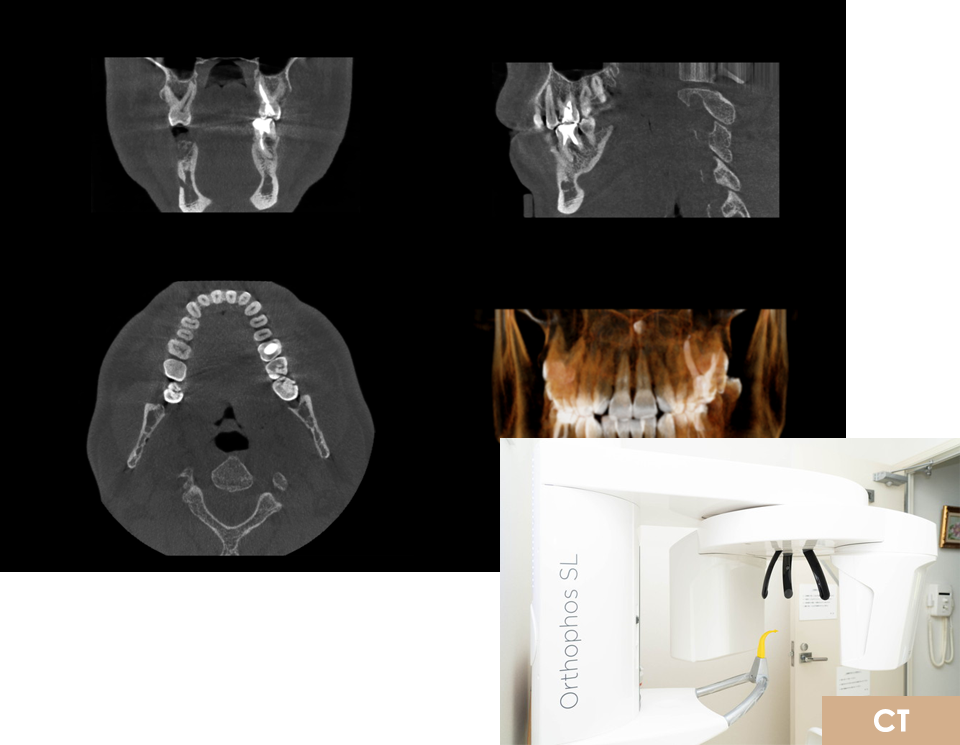

また、マイクロスコープ、AED、CTを常備し、

CT

インプラント治療において、口腔内の状態が把握できていないと神経や血管を傷つけてしまう可能性があります。そのため、術前にはCT撮影や模型での噛み合わせ分析などを行っています。

様々な資料や歯科用デジタルレントゲンに加えて、3DCT画像による手術部位の分析を徹底することで、より安心・安全にインプラント治療を行うことができます。

また、オペ直後にもCT撮影し、施術前の画像と比較してどのようにに埋入されてるかの説明をしております。

02CT・スキャナーによる

デジタル診断

歯科用デジタルレントゲンに加え、3DのCTによる手術部位の分析、全身の状態のチェックなど、資料をそろえて術前の分析を行います。また、3D口腔内スキャナー(プライムスキャン)を使用して採取したデータとCTによる分析結果を融合し、院内の3Dプリンターを使用してサージカルガイドを作製しています。サージカルガイドを用いることで、インプラント埋入時の位置や深さ、角度を細かく設定することができ、負担の軽減や手術時間の短縮に繋がります。